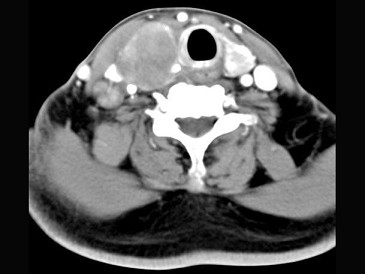

女,54岁,右侧颈部肿大近1年,近来病人有声嘶、吞咽困难,CT扫描如图,正确的描述或诊断是()

A.右侧甲状腺肿大,密度减低

B.增强扫描示甲状腺呈不规则强化团块影,其内有低密度区,病灶境界不清

C.右侧颈内静脉增粗,其内可见不规则充盈缺损区

D.甲状腺癌

E.右侧颈内静脉瘤栓形成

[多选题] 女,54岁,右侧颈部肿大近1年,近来病人有声嘶、吞咽困难,CT扫描如图,正确的描述或诊断是()A . 右侧甲状腺肿大,密度减低B . 增强扫描示甲状腺呈不规则强化团块影,其内有低密度区,病灶境界不清C . 右侧颈内静脉增粗,其内可见不规则充盈缺损区D . 甲状腺癌E . 右侧颈内静脉瘤栓形成

[多选题] 女,54岁,右侧颈部肿大近1年,近来病人有声嘶、吞咽困难,CT扫描如图,请选择正确的描述和答案()A . 右侧甲状腺肿大,密度减低B . 增强扫描示甲状腺呈不规则强化团块影,其内有低密度区,病灶境界不清C . 右侧颈内静脉增粗,其内可见不规则充盈缺损区D . 考虑甲状腺癌E . 右侧颈内静脉瘤栓形成

[多选题] 女性,54岁,右侧颈部肿大近1年,近来病人有声嘶、吞咽困难,CT扫描如图,请选择正确的描述和答案()。A . 右侧甲状腺肿大,密度减低B . 增强扫描示甲状腺呈不规则强化团块影,其内有低密度区,病灶境界不清C . 右侧颈内静脉增粗,其内可见不规则充盈缺损区D . 考虑甲状腺癌E . 右侧颈内静脉瘤栓形成